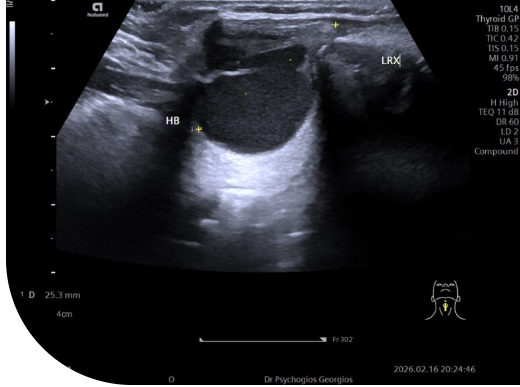

Κεφαλουραία απεικόνιση κύστης θυρεογλωσσικού ανάμεσα στο υοειδές οστό και το άνω τμήμα του θυρεοειδή χόνδρου.